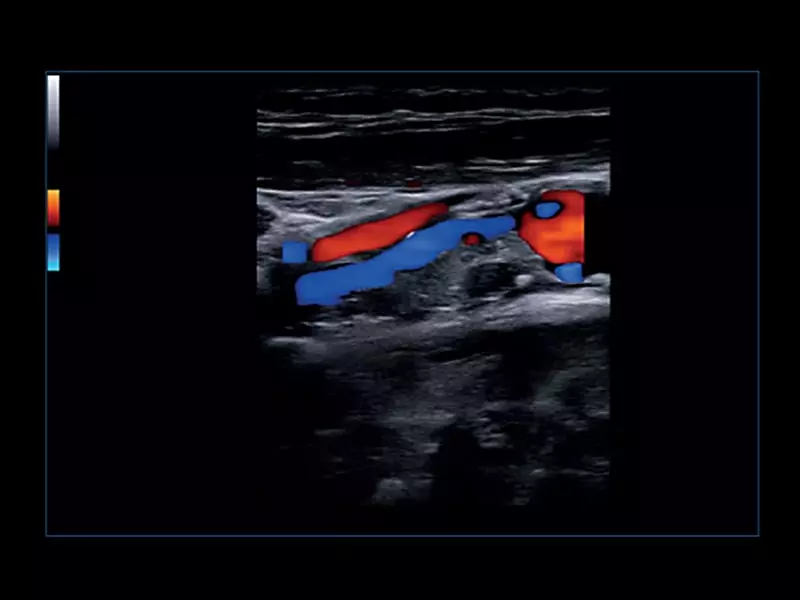

MyLab™Omega - Common Carotid Artery CFM

MyLab™Omega - Common Carotid Artery CFM